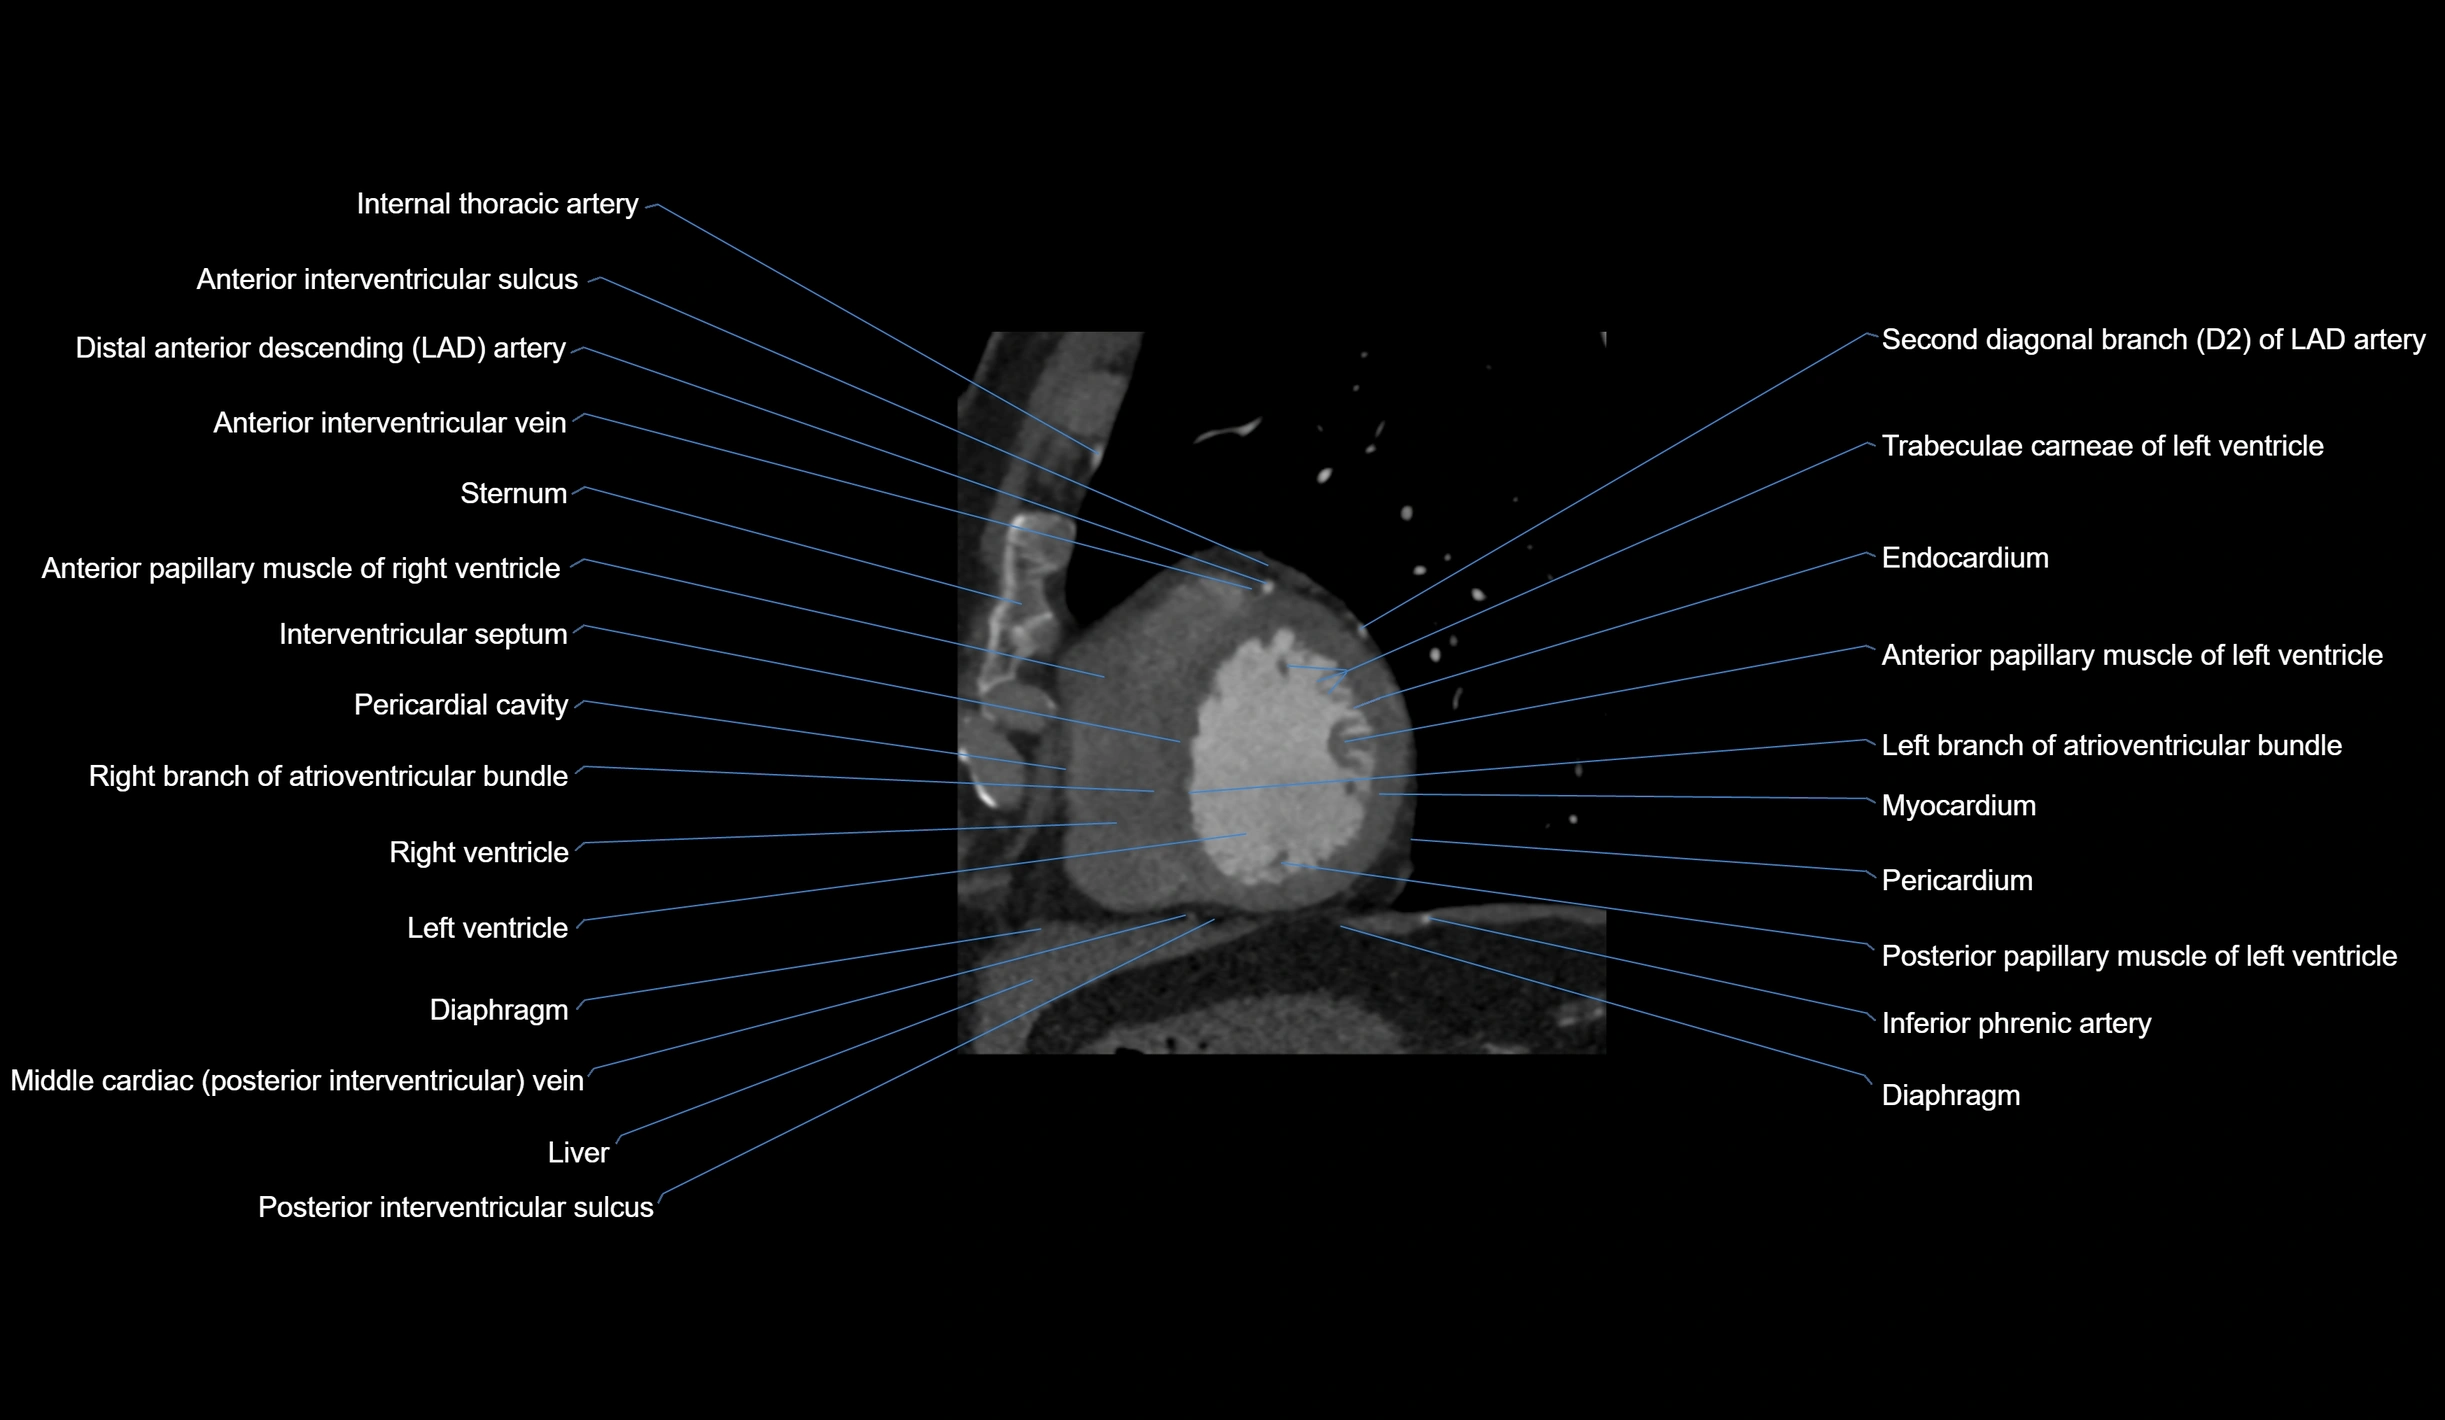

CT Appearance

Non-contrast CT (Calcium Scoring):

-

AM artery visualized for coronary calcium scoring

Calcified plaques appear as hyperdense foci; scored with Agatston method

CT Coronary Angiography (CCTA):

Best non-invasive modality for acute marginal artery visualization

Shows origin, course along the acute margin, and right ventricular branches

Detects stenosis, occlusion, calcified and non-calcified plaques, aneurysm, or anomalous course

Multiplanar reformats and 3D reconstructions help in pre-PCI and surgical planning

Critical for assessing right ventricular infarction risk in RCA disease

MRI image

CT images